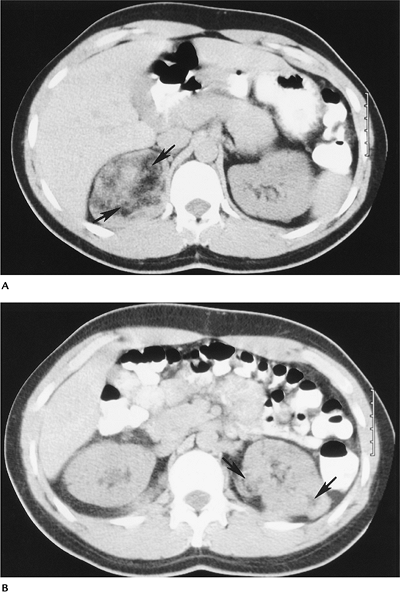

FIGURE 15-12 Tuberous sclerosis with renal angiomyolipomas. (A,B) Computed tomography (CT) images showing characteristic fat density masses (arrows), the largest in the right kidney.

|